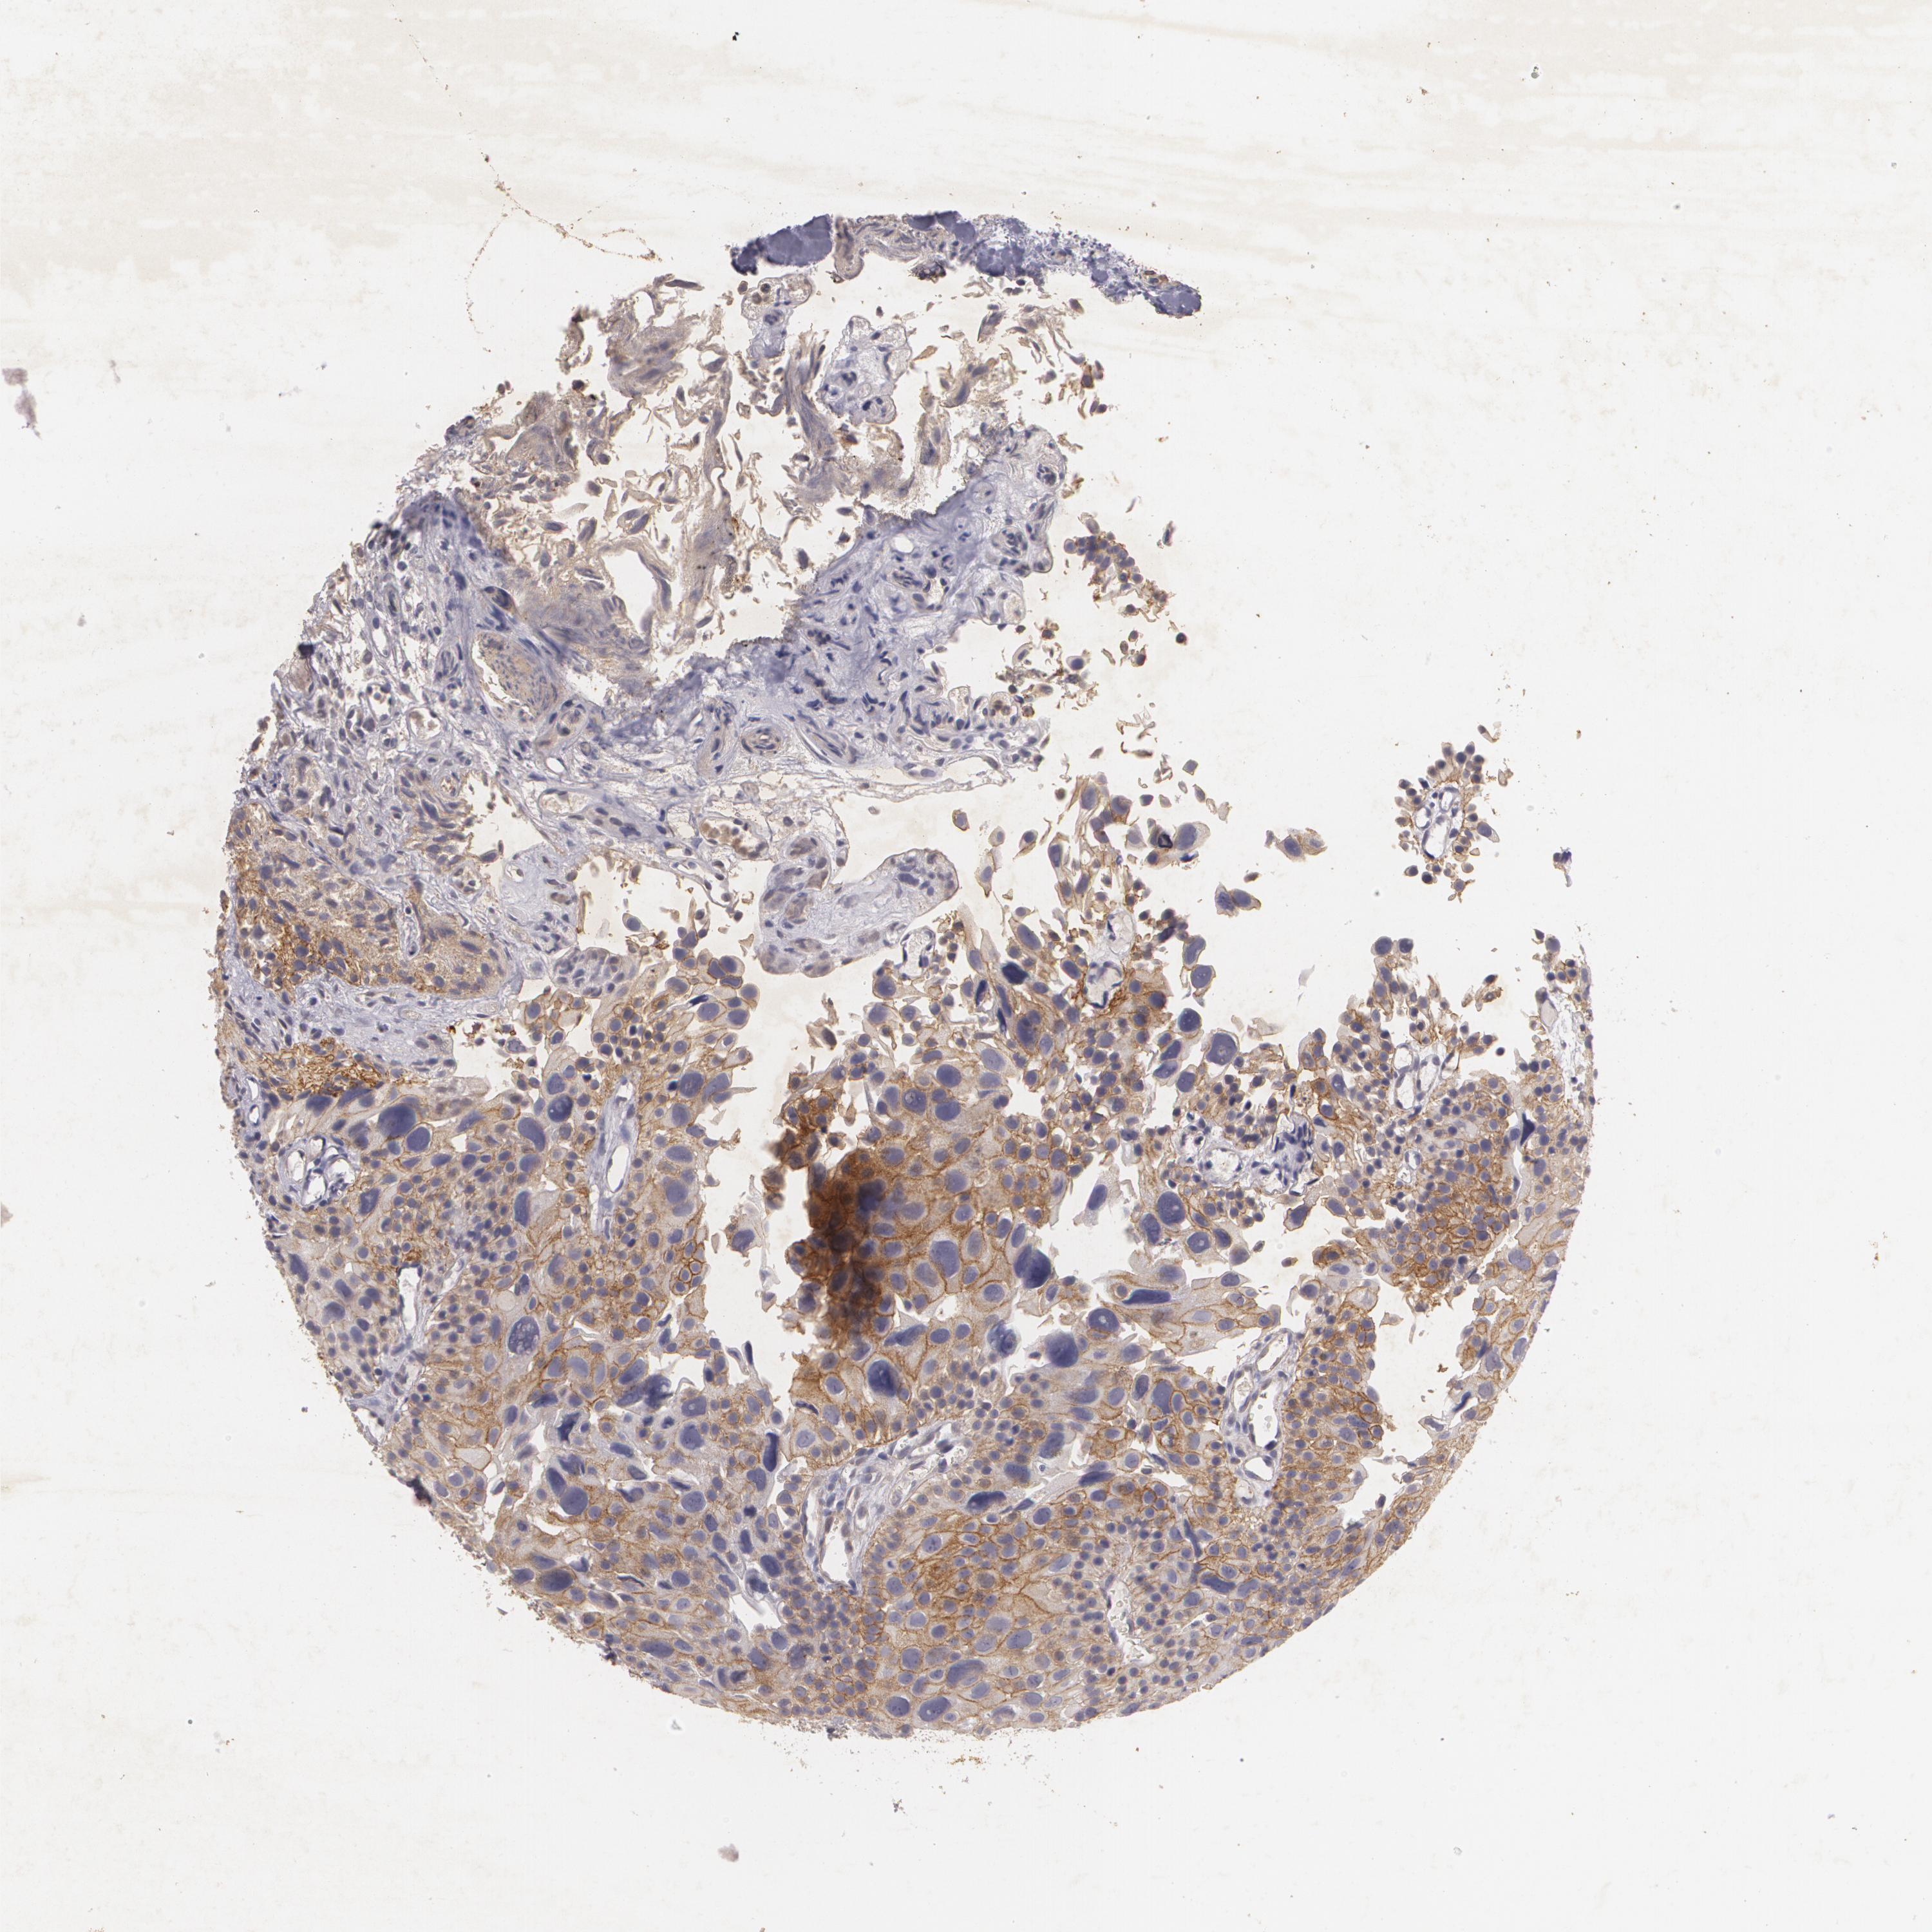

UROTHELIAL CANCER - Protein expressioni

A mouse-over function shows sample information and annotation data. Click on an image to view it in a full screen mode. Samples can be filtered based on level of antibody staining by selecting one or several of the following categories: high, medium, low and not detected. The assay and annotation is described here.

Note that samples used for immunohistochemistry by the Human Protein Atlas do not correspond to samples in the TCGA dataset.

Antibody stainingi

Antibody staining in the annotated cell types in the current human tissue is reported as not detected, low, medium, or high, based on conventional immunohistochemistry profiling in selected tissues. This score is based on the combination of the staining intensity and fraction of stained cells.

Each image is clickable and will lead to virtual microscopy that enables deeper exploration of all samples and also displays staining intensity scores, fraction scores and subcellular localization as well as patient and tissue information for each sample.

Antibody HPA016422

Antibody CAB001977

Staining

High

Medium

Low

Not detected

Intensity

Strong

Moderate

Weak

Negative

Quantity

>75%

75%-25%

<25%

None

Location

Nuclear

Cytoplasmic/membranous

Cytoplasmic/membranous,nuclear

Urothelial carcinoma, Low grade

Urothelial carcinoma, High grade

Adenocarcinoma, NOS